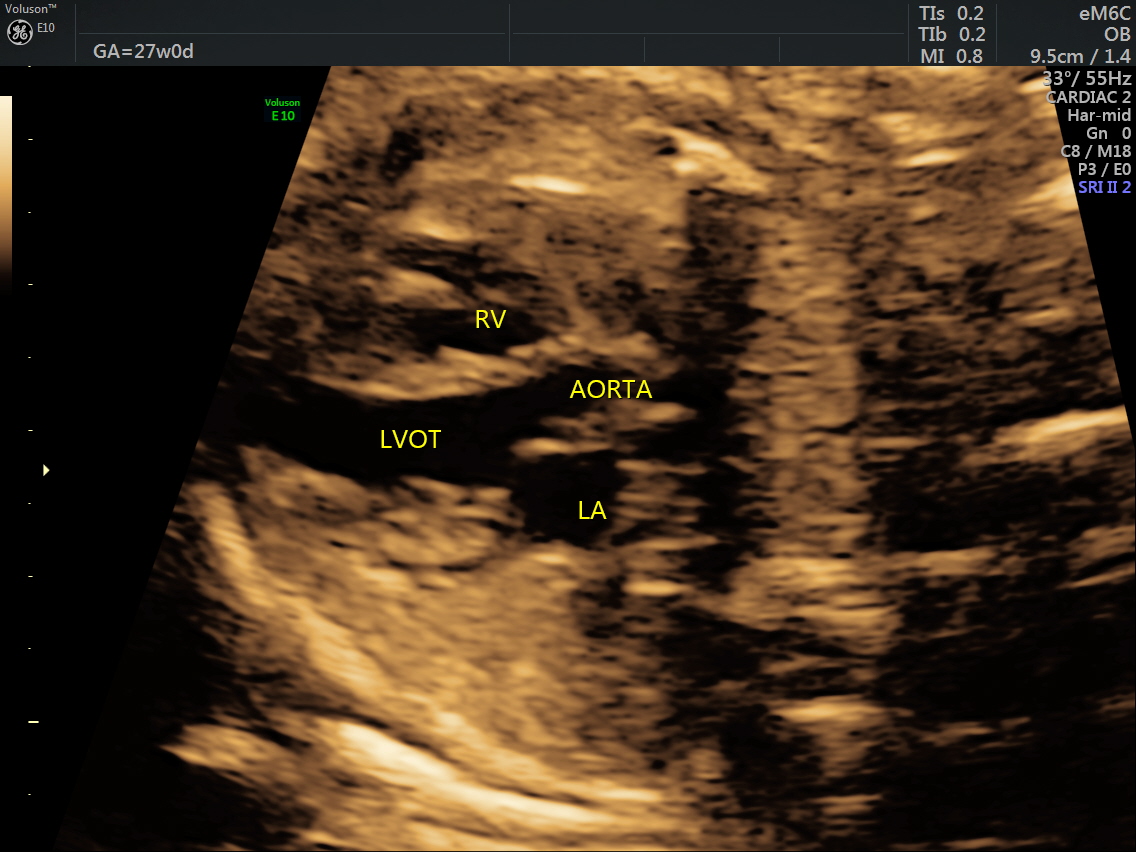

RT AORTIC ARCH_10 Published June 17, 2016 at 1136 × 852 in Rt aortic arch and aberrant left subclavian artery ← Previous Next →